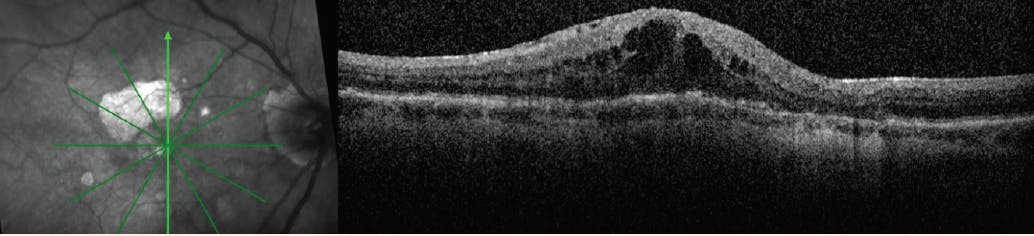

Case 2: Reducing Burden in Wet AMD

By Christina Y. Weng, MD, MBA

Patient History:

• 80-year-old woman with a 10-year history of dry age-related macular degeneration (AMD)

• Visits every 6 months for evaluation with consistent 20/25 VA

• Patient reports visual loss OD. VA of 20/60 OD and subretinal fluid (SRF) are documented (Figure 1).

<p>Figure 1. After presenting every 6 months with consistent 20/25 VA (left panel), the patient presented with 20/60 VA and new SRF (right panel).</p>

Click to view larger

Figure 1. After presenting every 6 months with consistent 20/25 VA (left panel), the patient presented with 20/60 VA and new SRF (right panel).

Intervention:

• Monthly aflibercept (Eylea, Regeneron) was administered for 3 months. VA improved to 20/40 OD, and SRF decreased but persisted (Figure 2, left panel). The patient asked if a new drug, which she heard reduces treatment burden, was an option.

• Brolucizumab (Beovu, Novartis) was administered after a conversation with the patient about risks of intraocular inflammation (IOI).

• A month later, VA improved to 20/30, and SRF had resolved (Figure 2, right panel).

• Brolucizumab was administered again after an interval of 8 weeks and again after 12 weeks. The patient remains stable at 20/30 VA with no signs of IOI.

<p>Figure 2. After three monthly doses of aflibercept (left panel), the patient responded well to brolucizumab therapy (right panel).</p>

Figure 2. After three monthly doses of aflibercept (left panel), the patient responded well to brolucizumab therapy (right panel).